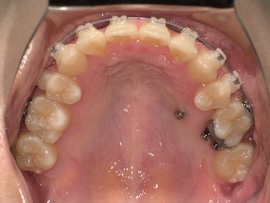

写真は撮っていないのでさらに1ヶ月後、

急に親知らずが出てきましたね。(笑)

無事に牽引ができたので、内側の装置も外れました。予定していたよりもかなり早く、牽引を始めてから約5ヶ月の時点です。